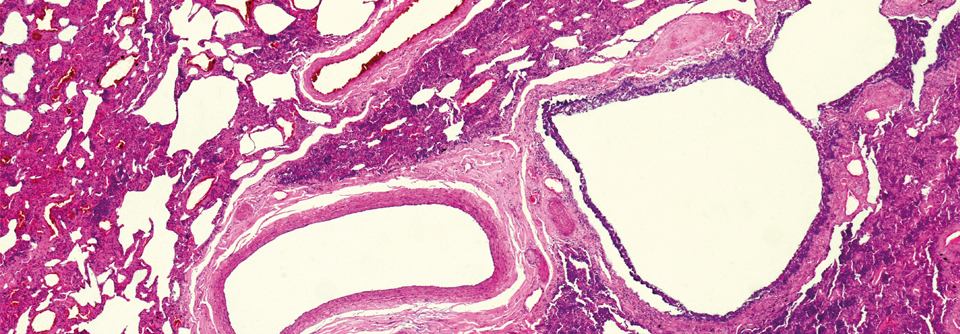

Häufig liegt Mosaikmuster vor

Histologisch finden sich bei der interstitiellen Lungenerkrankung im interstitiellen Gewebe…